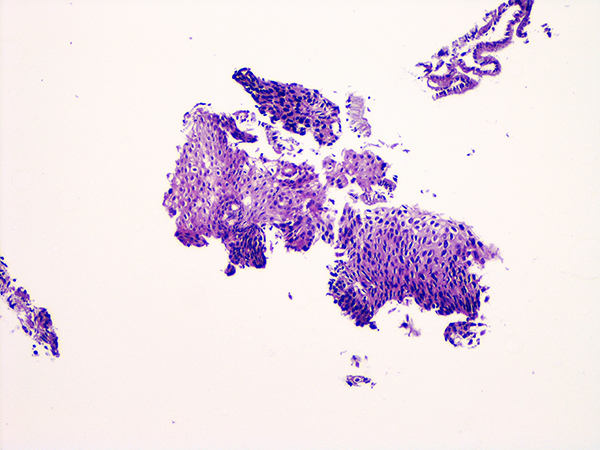

![]() Case 4

Soft Bx CIN 3

10x - Low Power |

Case 4

40x - High Power |